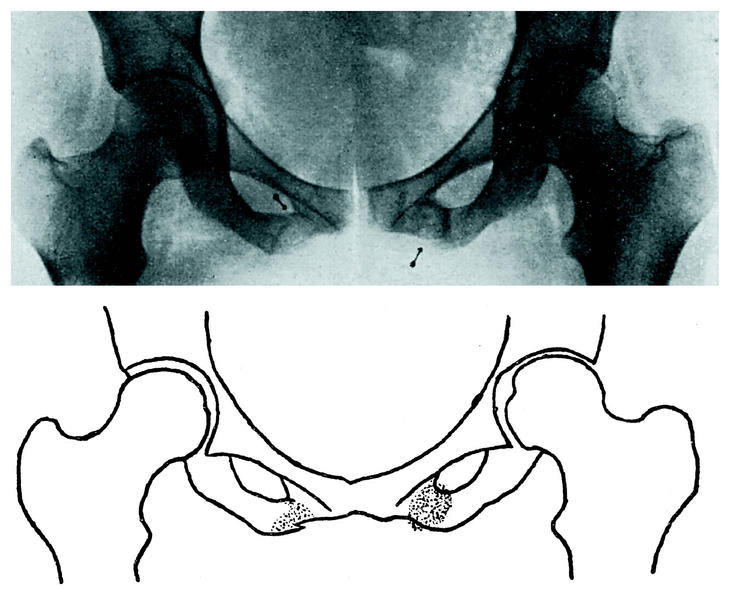

La radiografía (fig. 2) nos sorprende con una imagen doble de fractura de la rama isquiopúbica. En el lado izquierdo existe un callo redondeado de mayor transparencia a los rayos X en su parte central. En el lado derecho la imagen es la de una fractura reciente, incompleta, con decalcificación de la zona ósea a cuyo nivel asienta la fractura.

Figura 2.

La ausencia de un traumatismo reciente capaz de producir estas lesiones y la disparidad evolutiva de las mismas, en ambos lados, nos conduce al diagnóstico de fractura lenta en ambas ramas isquiopúbicas.

En el caso primero no llegamos a precisar la etiología exacta del proceso. El examen del resto del esqueleto no revelaba la presencia de enfermedad ósea sistematizada que pudiera servir de substrato a la bilateralidad de la lesión. Se trataba de una sirvienta que diariamente enceraba el «parquet» de la casa, en cuya tarea creemos encontrar el origen de la lesión, pues durante la danza realizada al encerar, ejecutaba movimientos de flexoextensión de cadera, unidos a esfuerzos de abducción alternantes. Este juego alternante podría ser la causa de la sobrecarga, fracturando el hueso en el punto donde se fusionan (ya tardíamente, del octavo al noveno año de la vida) los núcleos óseos del isquión y pubis. Podría influir en la etiología una disepifisiplasia isquipúbica sufrida anteriormente, como apunta Jordá, debido a la gran semejanza radiográfica de ambas lesiones. Seguramente la semejanza sería todavía mayor si se pudieran estudiar microscópicamente tanto las disepifisiplasias como este tipo de fracturas, en las que tejido osteoide debe ser la consecuencia de unos trastornos cuya patogenia no es clara, y en la que trastornos circulatorios de origen simpático deben jugar gran papel.